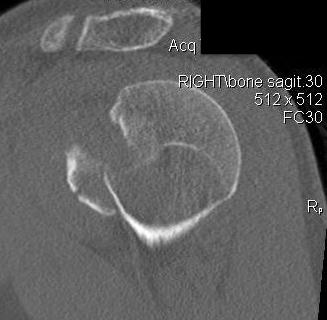

Scapular lateral

Center of the humeral head must be centered on the Y / Mercedes sign

Y is formed by

- coracoid anteriorly

- scapular spine posteriorly

- scapula body inferiorly

Normal scapular lateral

Posterior shoulder dislocation

Posterior shoulder dislocations